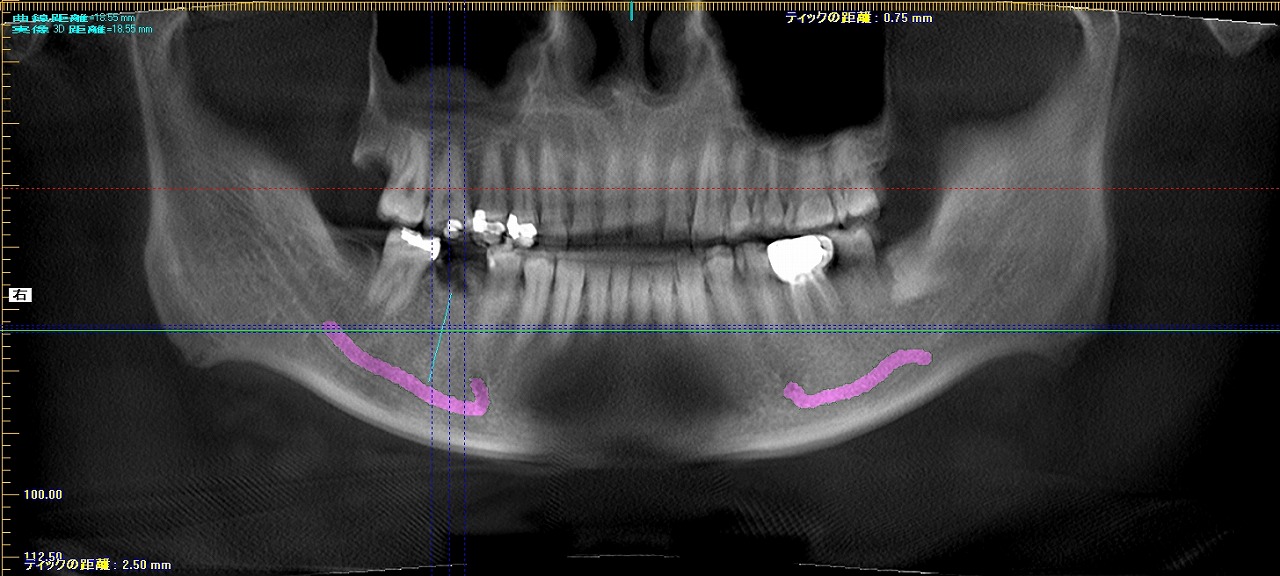

術前のCTになります

術前術後のパノラマになります